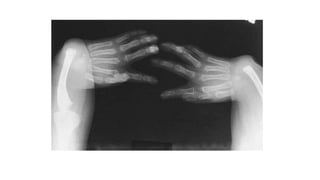

• Short and wide metacarpals and phalanges-

simulate Trident hand

• Proximal tapering of metacarpals and distal

tapering of phalanhges

Proximal pointing of metacarpals